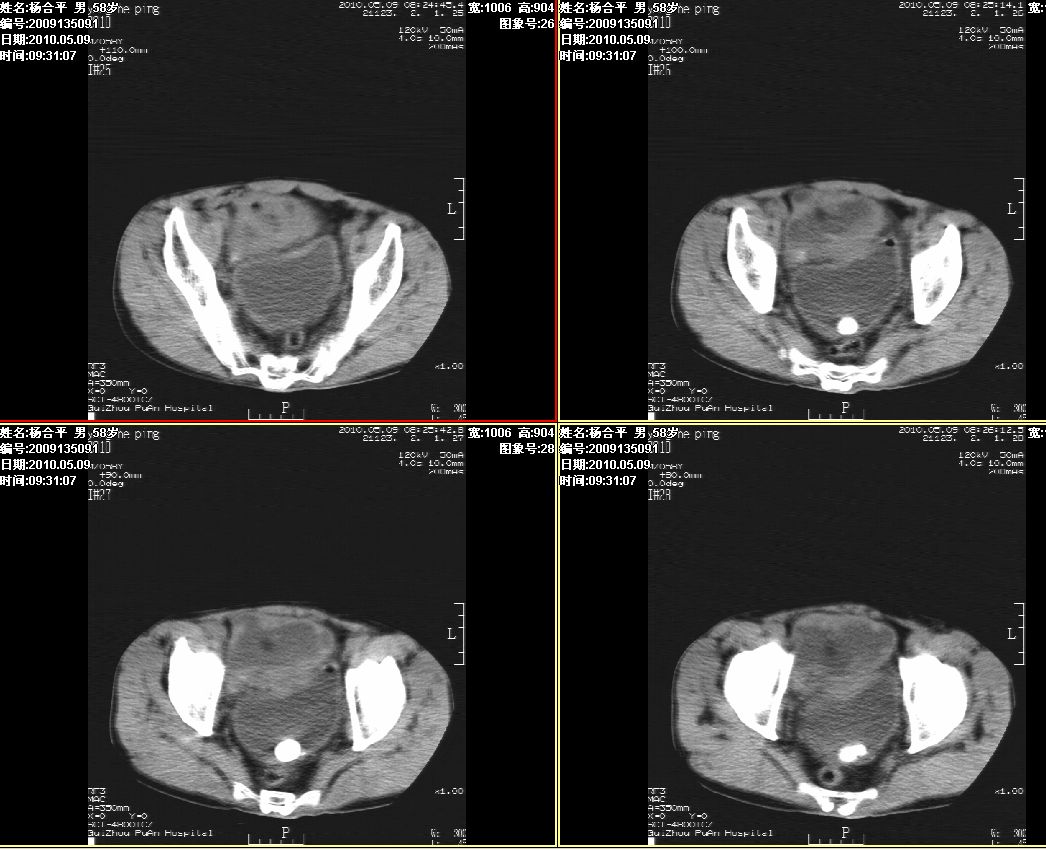

标题: CT26370:膀胱结石 [打印本页]

标题: CT26370:膀胱结石

杨某,男,75岁,进行性排尿困难2年,现行ct扫描图像如下,请大家看看,发表一下意见。

1.   膀胱内结石。(必要时采取俯卧位结石影位置会移动能进一步明确)

2.   膀胱前方所见,建议灌肠后ct增强扫描进一步明确。

不像大家想象的那么简单的病例。敢问大家一下,前方的是膀胱还是后方的是膀胱?

前方的是膀胱,后方的是膀胱憩室和结石。

膀胱巨大憩室内结石。